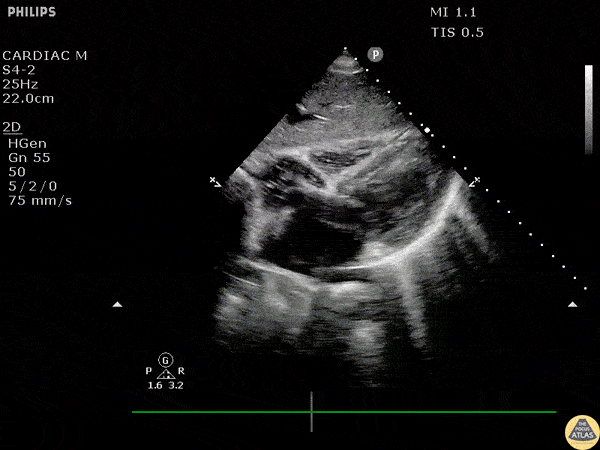

A middle aged male presents to the ED in cardiac arrest. Pre-hospital assessment showed asystole and AED indicated no shock advised. Subcostal echo revealed a quivering left ventricle indicative of fine ventricular fibrillation. Image courtesy of Robert Jones DO, FACEP @RJonesSonoEM Director, Emergency Ultrasound; MetroHealth Medical Center; Professor, Case Western Reserve Medical School, Cleveland, OH View his original post here